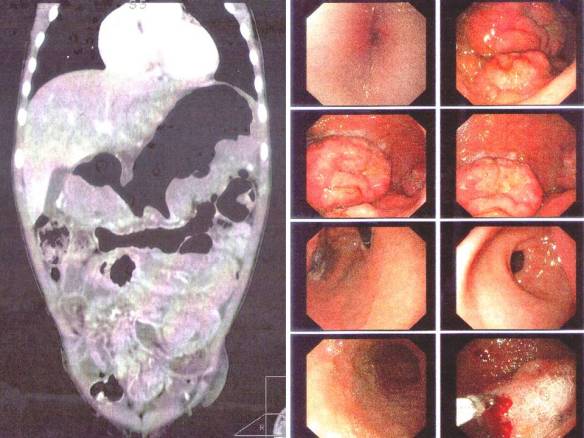

This 71-year-old lady was diagnosed with lymphoma and breast cancer. She underwent three rounds of chemotherapy (total of 24 cycles over a period of time). The treatment failed. Her health deteriorated. The family had to sell a house just to pay for the medical bills. At a loss, the family sought our help. The patient was started on our therapy. Her health improved! For sure, there is no need to sell another house to pay for this herbal treatment!